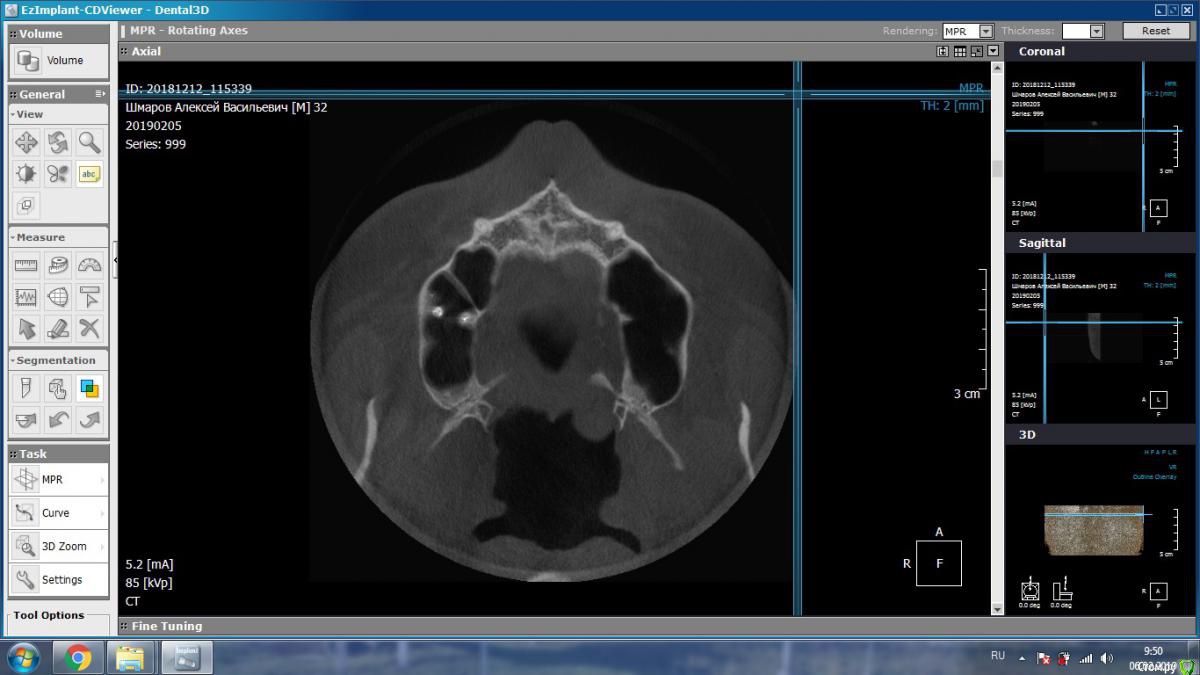

aleks.k Опубликовано 5 февраля, 2019 Автор Поделиться Опубликовано 5 февраля, 2019 Добрый день! Сделал КТ. Посмотрите пожалуйста.Есть 2 мнения очных стоматологов, пока никто из них КТ не видел, мнение на основании предыдущего панорамного снимка:1. Надо удалять 6 зуб справа2. Который и депульпировал 6 зуб сказал, что проблемы в 6 зубе нет, зуб мудрости нужно оттянуть брекетами. Размер файла 131 мб. http://fayloobmennik.cloud/7349278 Ссылка на комментарий

aleks.k Опубликовано 5 февраля, 2019 Автор Поделиться Опубликовано 5 февраля, 2019 Такие подойдут? Ссылка на комментарий

kramer Опубликовано 5 февраля, 2019 Поделиться Опубликовано 5 февраля, 2019 Судя по срезам, вероятнее причина в пульпите 7 зуба, возникшего в результате давления на него 8-ки. Ссылка на комментарий

DmitrySH Опубликовано 5 февраля, 2019 Поделиться Опубликовано 5 февраля, 2019 Такие подойдут? В Аксиальной проекции покажите еще несколько срезов Ссылка на комментарий

aleks.k Опубликовано 6 февраля, 2019 Автор Поделиться Опубликовано 6 февраля, 2019 Срезы Ссылка на комментарий

aleks.k Опубликовано 6 февраля, 2019 Автор Поделиться Опубликовано 6 февраля, 2019 Еще один срез, может быть более удачный чем первые в этой проекции Ссылка на комментарий

DmitrySH Опубликовано 6 февраля, 2019 Поделиться Опубликовано 6 февраля, 2019 Срезы Очень хорошо. Теперь как первые три, но увеличить 16 зуб. Остальные нам мало интересны, пазуха тоже Ссылка на комментарий